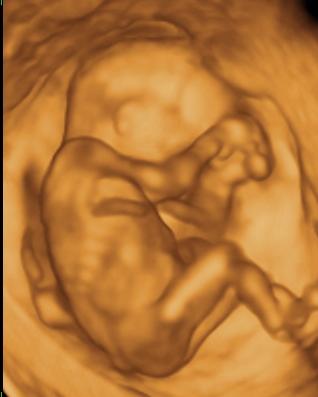

Tök sokára jutottam be, mert ugye nem volt időpontom. Meg ultrahangozott a doki, hát érdekes volt. Először nem mondott semmit, csak a végén közölte, hogy ok, most menjek el sétálni, negyed órára és majd visszahívnak, mert nem jól fekszik a baba

én még ilyen nehézkes nyaki redő mérést nem pipáltam... ok lementem gyalog a lépcsőn, ittam egy kávét, majd fel gyalog a negyedikig. Na ez meg is tette hatását- mikor visszahívtak, elkezdte mérni, megmérte vagy tízszer (!!!) a nyaki redőt. Nem mondott semmit. De én láttam alul a sarokban, hogy oda volt írva az NT, és hogy folyton ilyeneket mért, hogy 2,1,2,2,2,3....stb. mindig ekörül. Már törölgette a homlokát, összenéztek az asszisztenssel... kezdtem nagyon unni. Mondja egy idő után, hogy hát ő nem érti, de neki meg sem közelíti a 3-at.... mondja max 2.3-at mért idáig. Na mondom, az jobban hangzik, mint a 3.3. Akkor utána elkezdett a gyerek pörögni, kiegyenesedett, akkor is ilyeneket méregetett, majd a lepénytapadásra semmit nem mondott

, és mikor a gyerek kicsit hátrahajtotta a fejét, na akkor mért 2,8-3-at. És utána mondta, hogy ne haragudjak, de akkor ezt írja be, mert ha kicsit hátrahajtja a fejét, akkor vastagabb. De, szerinte nincs az 3 se, mindenesetre menjek el genetikai tanácsadásra....